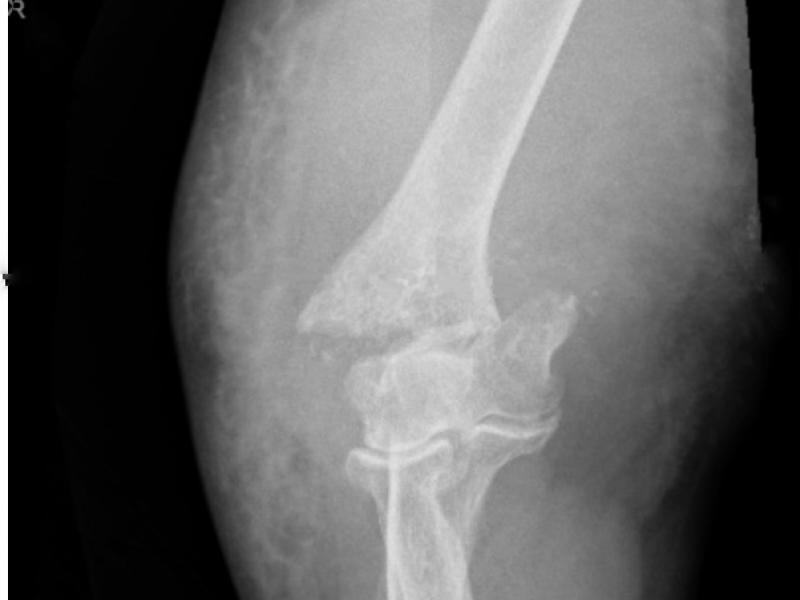

What's the diagnosis?  By Dr. Geno Marrone

EM Daily

September 08 2021

A 76 yo female presents after a fall on an outstretched